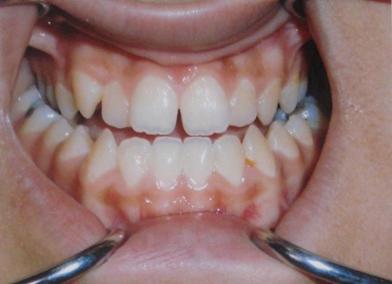

Image : Endoalvéolie bilatérale sévère associée à une D.D.M. par macrodontie, pouvant faire penser à une exoalvéolie mandibulaire.

Les Anomalies Mandibulaires

Endoalvéolie Mandibulaire

Définition

En général, la rétroposition associée à l’endoalvéolie mandibulaire laisse croire à une endognathie mandibulaire, ce qui fait que cette anomalie n’existe pas à l’état pur. Elle est caractérisée par :

- Étage inférieur diminué.

- Vestibuloclusion des secteurs latéraux maxillaires.

Image : Orthodontie pédiatrique Archives – ODF